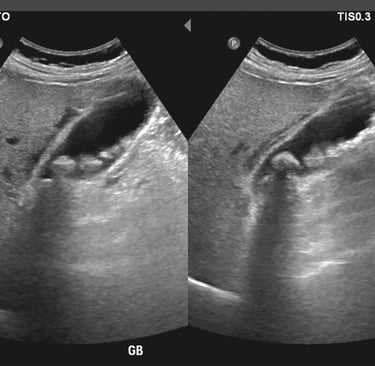

A lot of people go through life without realizing that tiny stones may already be forming inside their gallbladder. These are called gallstones. Most people never experience any symptoms and may only be diagnosed incidentally with routine whole abdominal ultrasound. However, some of my patients do experience severe abdominal pain that sends them to my clinic, or worse, to the emergency department. Understand gallstone is the main topic for today to help patients recognize early symptoms and seek proper medical care before complications occur.

Doc Damian, what are gallstone, why are they bothersome to some people? Gallstones are hardened deposits of digestive fluid that form in the gallbladder, a small organ just below the liver. The main function of the gallbladder is to store bile, which helps digest fats. When the substances in bile become imbalanced, they can crystallize and form stones. I’m sure, you did not know that there are 2 types of gallstones: cholesterol stones and pigment stones. Cholesterol stones are the most common type, about 80% of cases – they form when bile contains too much cholesterol. The latter, pigment stones, are smaller and darker colored which is made up of bilirubin – and are often associated with liver disease or blood disorders.

As I had mentioned earlier, gallstones may be silent for a long period of time until pain is experienced by the patient. So, what type and characteristic of pain do we need to watch out for? The pain is in the right upper quadrant of the abdomen, that occurs after eating fatty meals and can radiate to the right shoulder or scapular area that may be associated with nausea/vomiting or bloated. Pain will only occur when a stone is already blocking the duct. If left untreated, gallstones can lead to serious complications such as acute cholecystitis (infection of the gallbladder), pancreatitis, obstruction and jaundice – when this are observed, urgent medical attention is warranted.